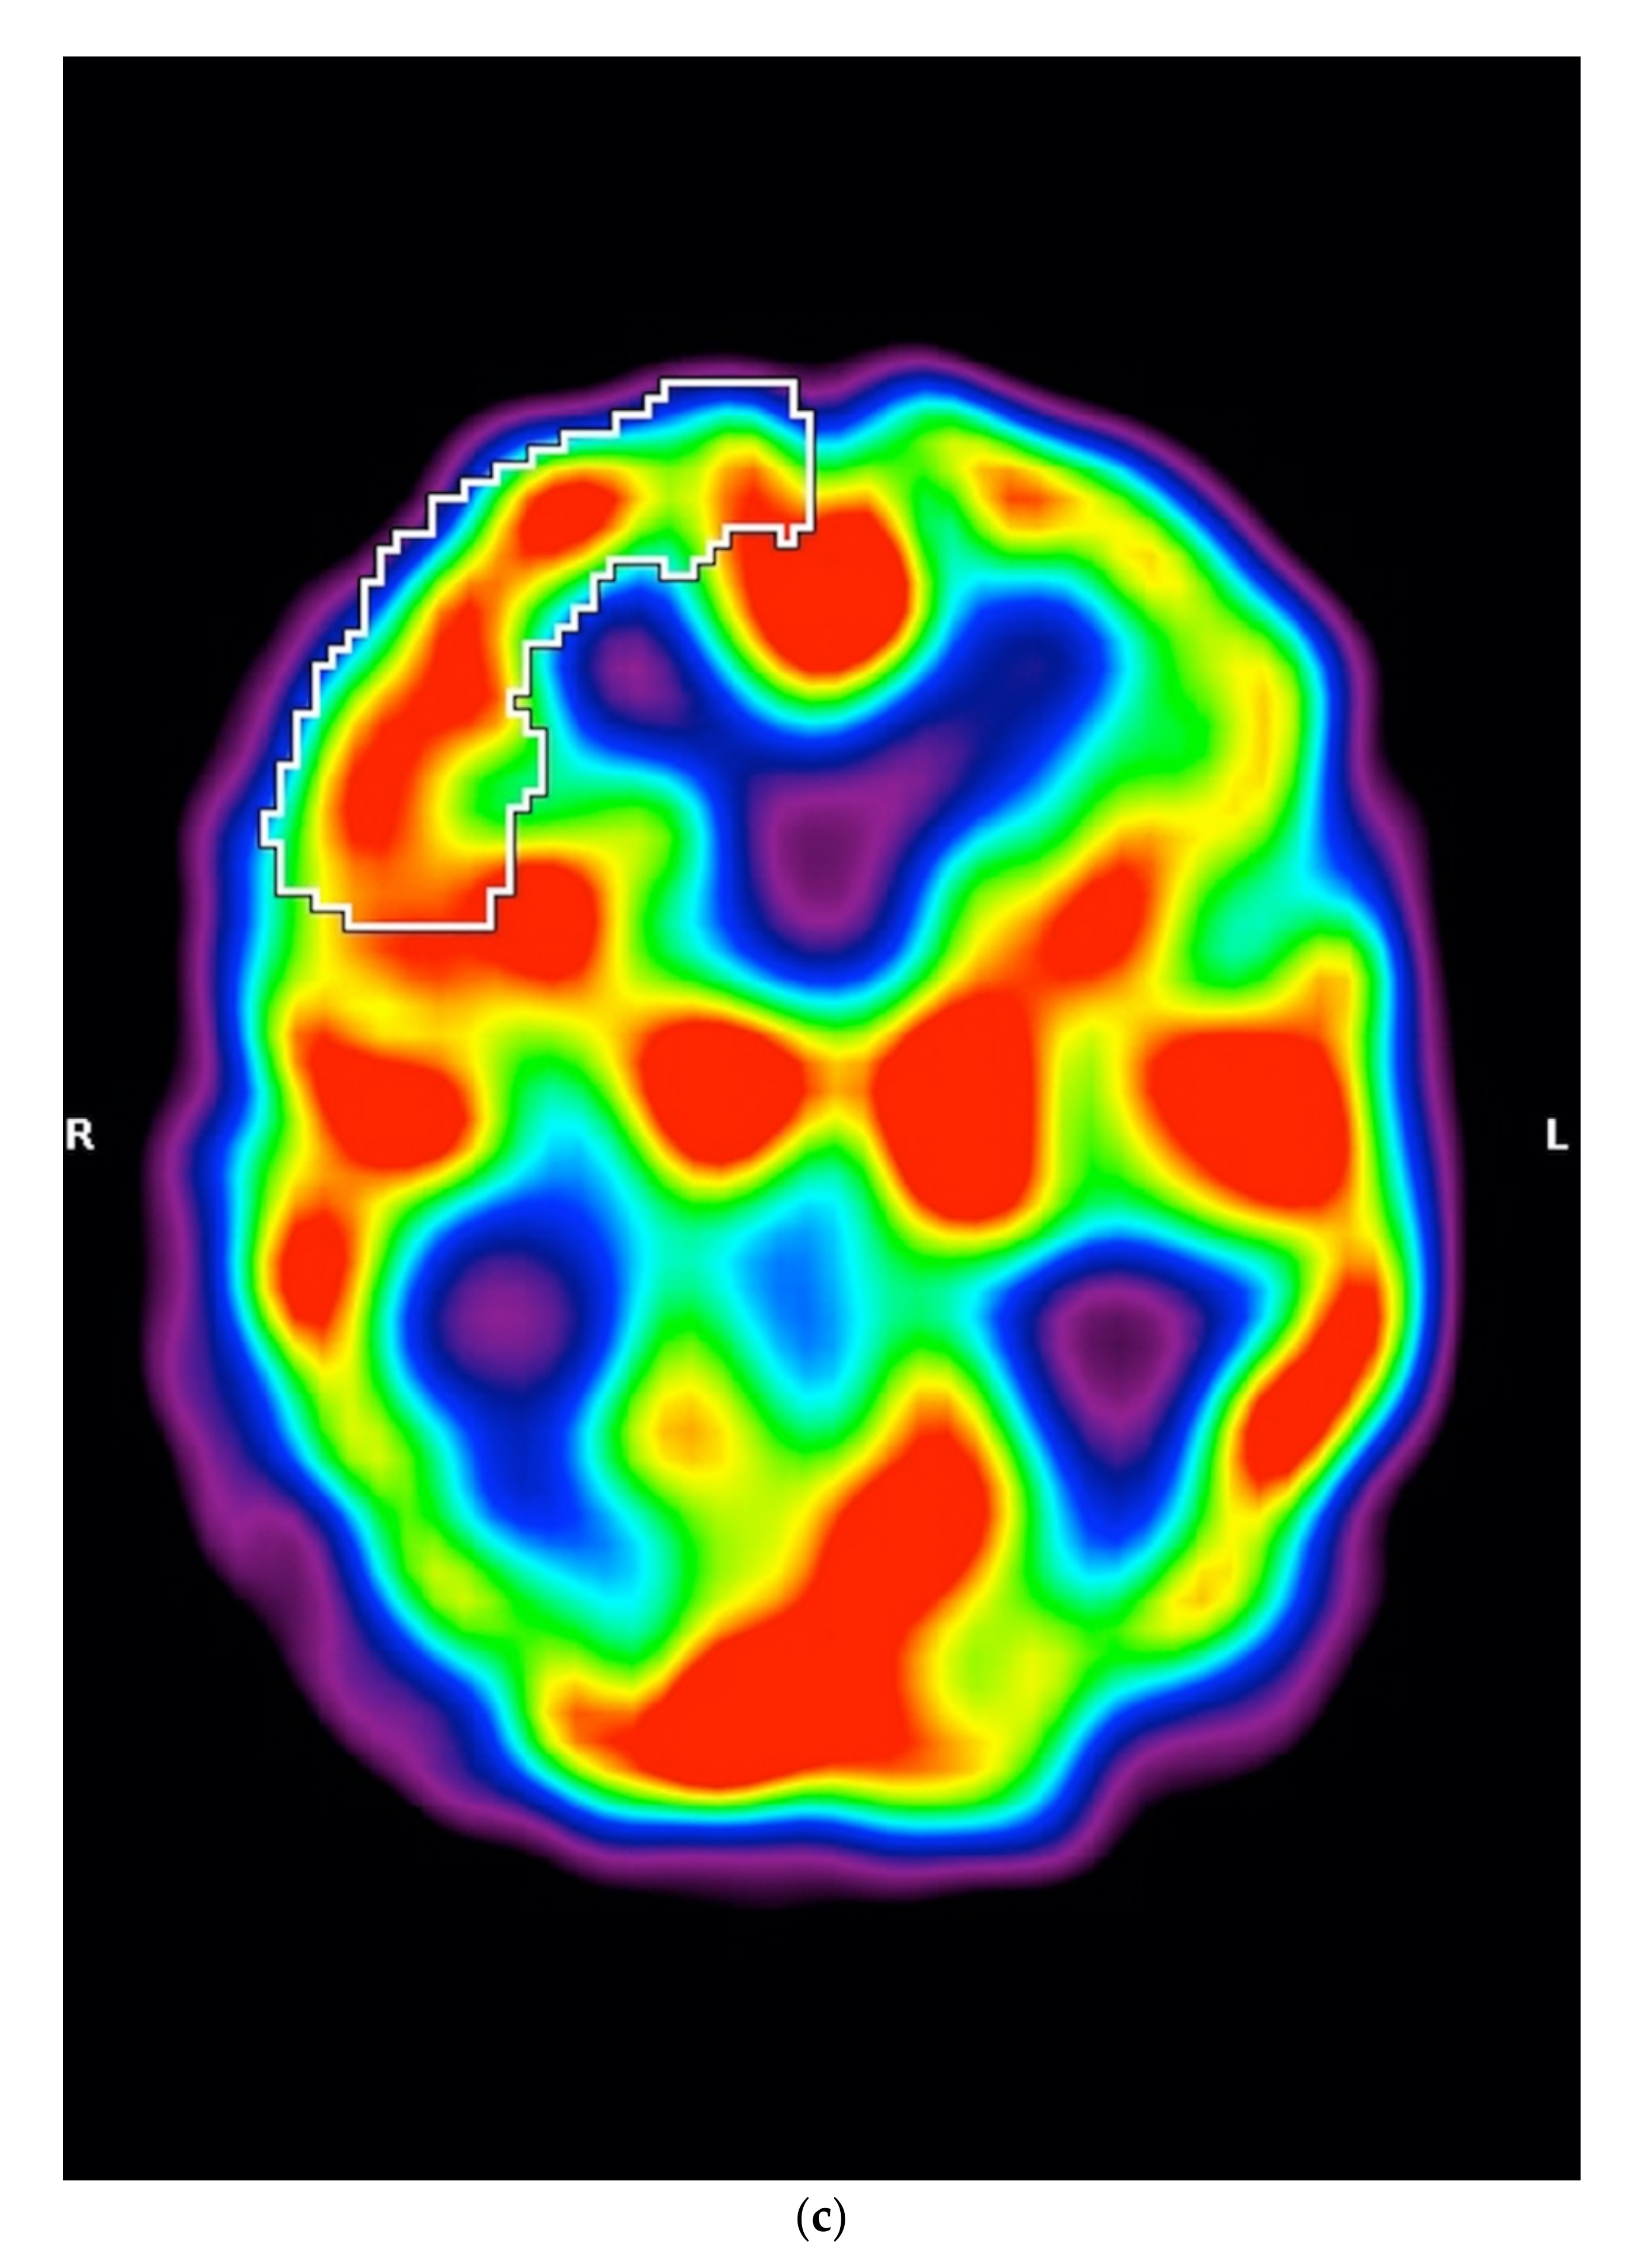

3.2. SPECT

5.1.3. SPECT